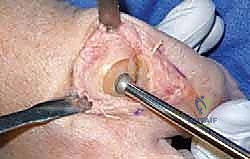

- ما هي؟ جراحة يتم فيها "تنظيف" المفصل. يقوم الجراح بإزالة النتوءات العظمية (Bone Spurs) من أعلى المفصل، بالإضافة إلى إزالة جزء صغير من أعلى رأس عظمة المشط.

- الهدف: إزالة العائق الميكانيكي الذي يمنع حركة الإبهام لأعلى، مما يخفف الألم ويحسن نطاق الحركة.

3. استبدال المفصل (Arthroplasty) - الثورة الطبية

- لمن تصلح؟ للمرضى في المراحل المتقدمة (2، 3، وأحياناً 4) الذين يرفضون دمج المفصل ويرغبون بشدة في الحفاظ على حركة المفصل.

- ما هي؟ استبدال أسطح المفصل التالفة بمواد صناعية. وهنا تبرز التقنية الأحدث والأكثر نجاحاً عالمياً: **تقنية Arthrosurface